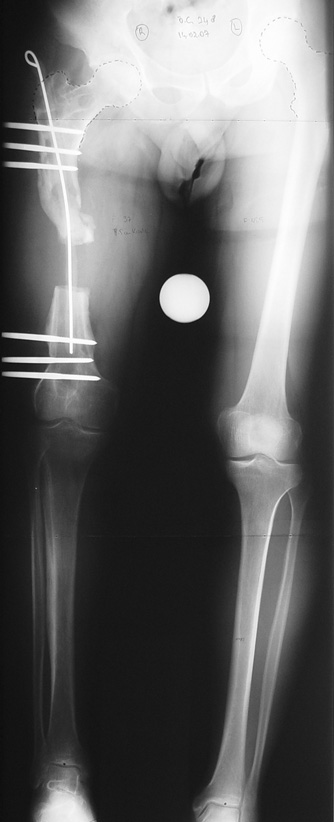

Femur Osteomyelit

Kas ve iskelet sistemi enfeksiyonları, sık karşılaşılan bir sorundur. Yeni evreleme sistemleri, gelişmiş cerrahi teknikler, ve hiperbarik oksijen tedavisi gibi destek tedavileri sayesinde kronik osteomiyelit tedavisi son 20 yıl içinde büyük ölçüde değişmiştir.

Uygun radikal debridman tüm nekrotik kemik ve yumuşak dokuların çıkartılmasını gerektirir, ve sıklıkla uzuvda instabiliteye neden olur. Kalan kemik ve yumuşak doku defektinin bir şekilde fiksasyonu ve rekonstrüksiyonu gereklidir. İlizarov’un ortaya koyduğu distraksiyon osteogenezi yöntemi, kaynamanın elde edilmesi, deformitenin düzeltilmesi, bacak boy eşitsizliğinin giderilmesi ve segmental defektlerin rekonstrükte edilmesi için başarıyla kullanılmaktadır.

Vaka 1